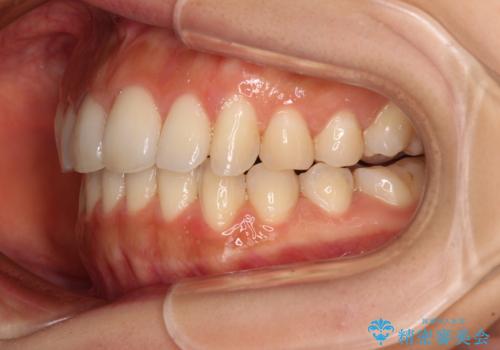

カリエールディスタライザーを併用した、咬み合わせ改善のインビザライン矯正

- 飛び出した前歯と口元の突出感を気にして来院された患者様です。

奥歯の咬み合わせを見ると、上顎が下顎に対して相対的に前方にありました。

口元の突出感を改善するためには、上顎臼歯を後方に移動させた咬み合わせにする必要があります。

インビザライン単体で改善することも可能ですが、達成する可能性が高くないため、カリエールディスタライザーという補助装置を併用して、より確実性を上げることとしました。

奥歯の咬み合わせを改善しながら、並行してインビザラインで歯列を整えることとしました。

カリエールディスタライザーを併用したことで、確実かつ短期間で治療を終えることができました。